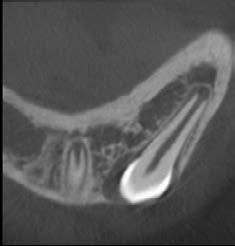

Endodontie

Der Patient berichtete anamnestisch über ein Trauma im linken vorderen Oberkiefer. Mit dem 3D R100 wurde ein DVT des Oberkiefers erstellt. Sowohl die sagittale, als auch die vertikale Ansicht zeigten eine horizontale Fraktur im bukkalen Bereich des Zahnhalses des endodontisch behandelten linken seitlichen Schneidezahnes. In der Sagittalebene stellte sich auch eine Perforation der bukkalen Knochenlamelle dar.